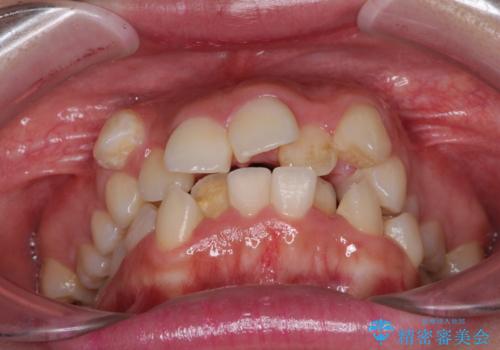

著しい叢生と顎骨のズレ ワイヤー装置による抜歯矯正

- 前歯の著しい叢生や八重歯を気にして来院された患者様です。

上下の顎がずれており、上下の正中は歯1本分の差がありました。

上下左右の小臼歯4本を抜歯し、極力正中を合わせるように矯正治療を始めていくこととしました。

咬み合わせの乱れが著しく、治療途中で一部反対咬合となってしまいました。

アンカーなどをうまく使用して、3年の期間を要してきれいに仕上げることができました。